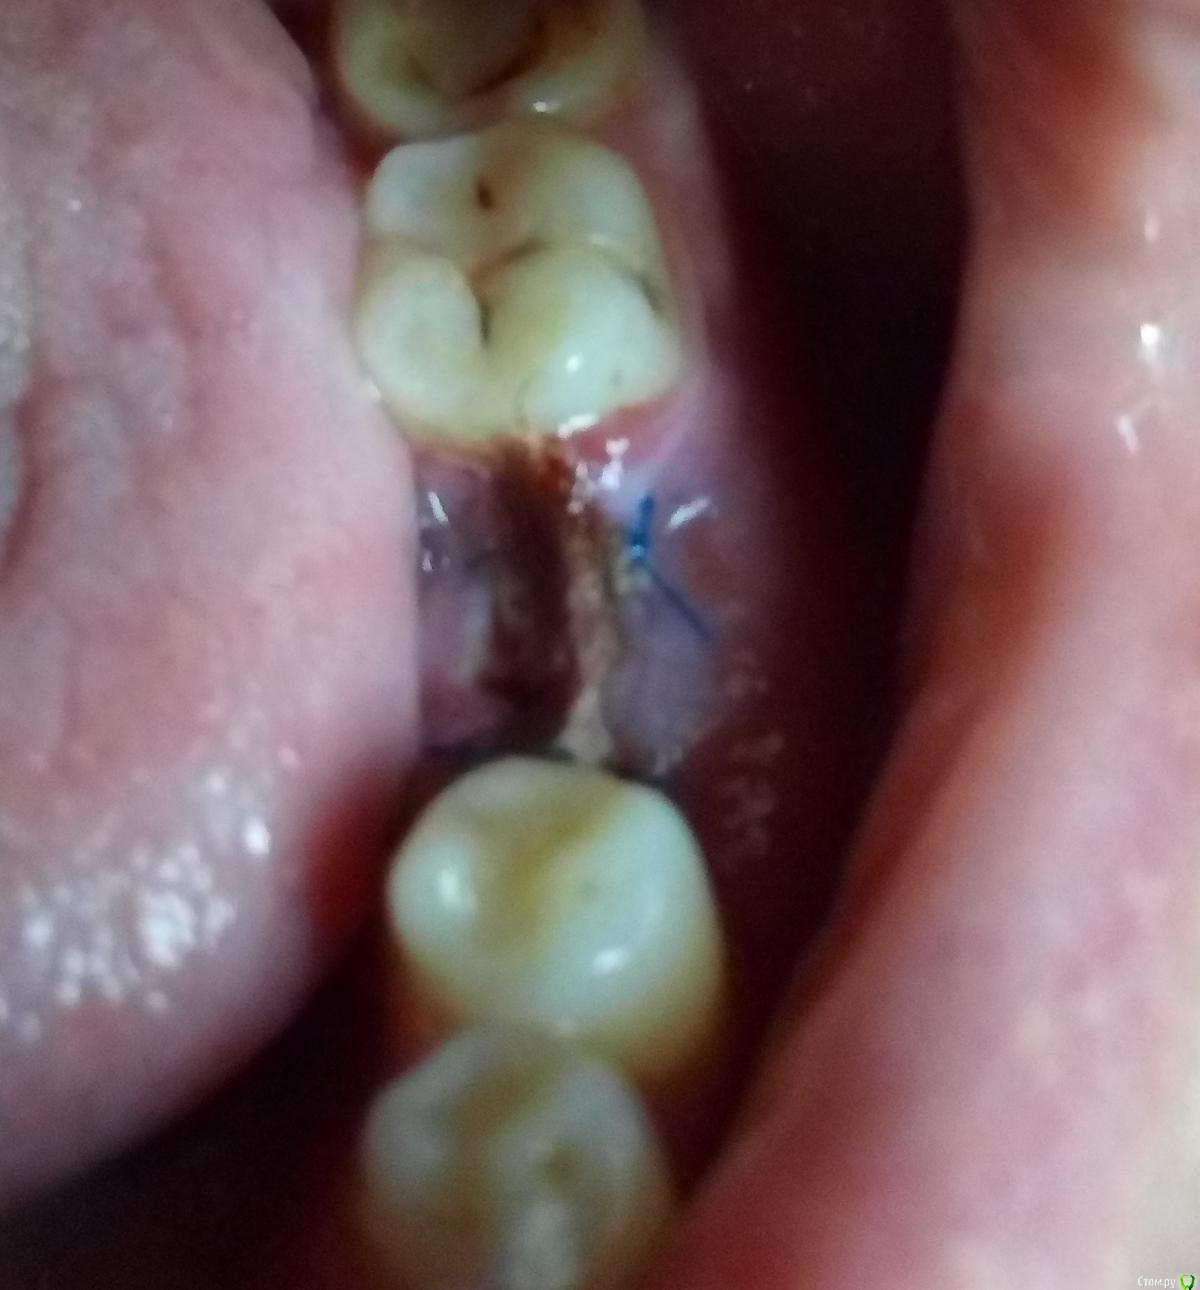

Устала Опубликовано 26 апреля, 2018 Автор Поделиться Опубликовано 26 апреля, 2018 Уважаемы доктора! Вот!Ситуация во рту - это сегодня после очередного упражнения доктора в кройке и шитье.Может уже бежать к другому, что скажите? Ссылка на комментарий

Устала Опубликовано 26 апреля, 2018 Автор Поделиться Опубликовано 26 апреля, 2018 (изменено) Вот ещё. Тут может получше.Сегодня доктор хотел выкрутить формирователь, но не смог. Достал другой формирователь, наверное, хотел поменять его, но вот не случилось. Отправил так. Изменено 26 апреля, 2018 пользователем Устала Ссылка на комментарий